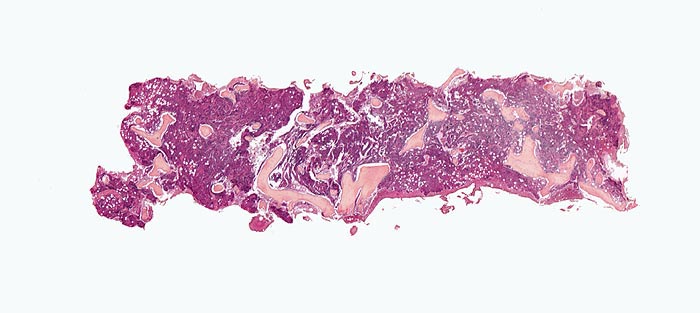

Morphologie

Morphologische Merkmale:

• Osteosklerose: verplumpte und breite Knochenbälkchen.

• Kollagenfibrose.

• Dilatierte Sinusoide mit intrasinusoidaler Blutbildung.

• Vermehrung von atypischen, in Gruppen liegenden Megakaryozyten mit abnorm lobulierten Kernen.

• Nacktkernige (zytoplasmaarme) und vergrösserte Megakaryozyten.

• Hyperplastische ausreifende Myelopoese.

• Hypoplastische Erythropoese.

• Retikulinfaserfibrose des Marks vorhanden aber in der HE Färbung schwierig quantifizierbar.